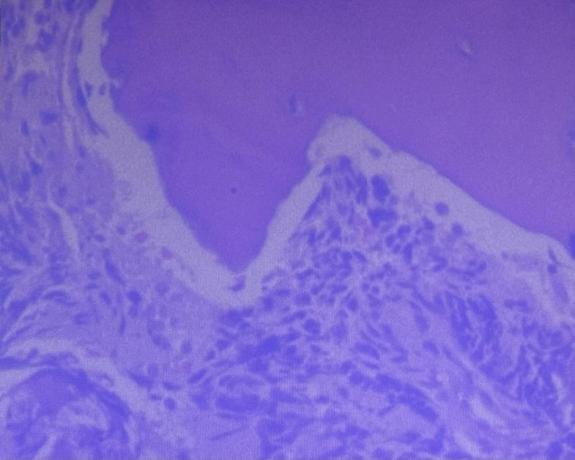

2021.1.13行“B超引导下右侧腹膜后肿物穿刺活检术+骨髓活检术+骨髓穿刺术”,术后病理:镜下可见小圆蓝肿瘤细胞成片分布,结论为(腹膜后)低分化神经母细胞瘤(高MKI)。

术后病理:送检肿瘤组织大小约5 cm×2.5 cm×1.5 cm,镜下见低分化的神经母细胞瘤成分,伴广泛坏死、出血、含铁血黄素沉着、组织细胞及炎细胞浸润,可见散在钙化。

淋巴结:4区2/4、3区1/6、5区1/3见肿瘤转移,9区0/1未见肿瘤转移。

病理结论:(腹膜后)符合低分化神经母细胞瘤化疗后改变。